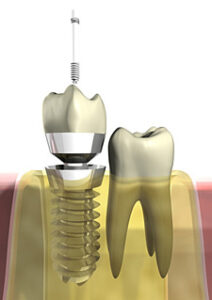

Resektion heißt soviel wie Abschneiden und genau darum geht es bei einer Wurzelspitzenresektion. Die entzündete Spitze einer Zahnwurzel wird gekappt, das entzündete Gewebe entfernt und der Zahninnenraum gründlich gereinigt. Danach wird der verbleibende Hohlraum versiegelt. Das Ganze geschieht bei einem kleinen operativen Eingriff. Ehe dieser vorgenommen wird, wird zunächst geprüft, ob eventuell eine Wurzelbehandlung ausreicht. Dazu werden Röntgenbilder erstellt und ausgewertet. Häufig ist die Wurzelspitzenbehandlung die letzte Möglichkeit einen Zahn zu erhalten. Falls möglich, wird daher zumeist erst eine Wurzelkanalbehandlung angestrebt. Hierbei wird die alte Wurzelfüllung entfernt, der Zahninnenraum desinfiziert und eine neue Wurzelfüllung eingebracht. Reichen diese Maßnahmen nicht aus, kann die Wurzelspitzenresektion in Betracht gezogen werden.

Wie wird eine Wurzelspitzenresektion durchgeführt?